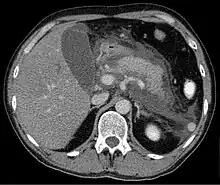

Computed tomography

Regarding the need for computed tomography, practice guidelines state:

CT is an important common initial assessment tool for acute pancreatitis. Imaging is indicated during the initial presentation if:

- the diagnosis of acute pancreatitis is uncertain

- there is abdominal distension and tenderness, fever >102 F (38,9 C), or leukocytosis

- there is a Ranson score > 3 or APACHE score > 8

- there is no improvement after 72 hours of conservative medical therapy

- there has been an acute change in status: fever, pain, or shock

CT is recommended as a delayed assessment tool in the following situations:

- acute change in status

- to determine therapeutic response after surgery or interventional radiologic procedure

- before discharge in patients with severe acute pancreatitis

Abdominal CT should not be performed before the first 12 hours of onset of symptoms as early CT (<12 hours) may result in equivocal or normal findings.

CT findings can be classified into the following categories for easy recall:

- Intrapancreatic – diffuse or segmental enlargement, edema, gas bubbles, pancreatic pseudocysts and phlegmons/abscesses (which present 4 to 6 wks after initial onset)

- Peripancreatic / extrapancreatic – irregular pancreatic outline, obliterated peripancreatic fat, retroperitoneal edema, fluid in the lessar sac, fluid in the left anterior pararenal space

- Locoregional – Gerota's fascia sign (thickening of inflamed Gerota's fascia, which becomes visible), pancreatic ascites, pleural effusion (seen on basal cuts of the pleural cavity), adynamic ileus, etc.

The principal value of CT imaging to the treating clinician is the capacity to identify devitalized areas of the pancreas which have become necrotic due to ischaemia. Pancreatic necrosis can be reliably identified by intravenous contrast-enhanced CT imaging,[22] and is of value if infection occurs and surgical or percutaneous debridement is indicated.